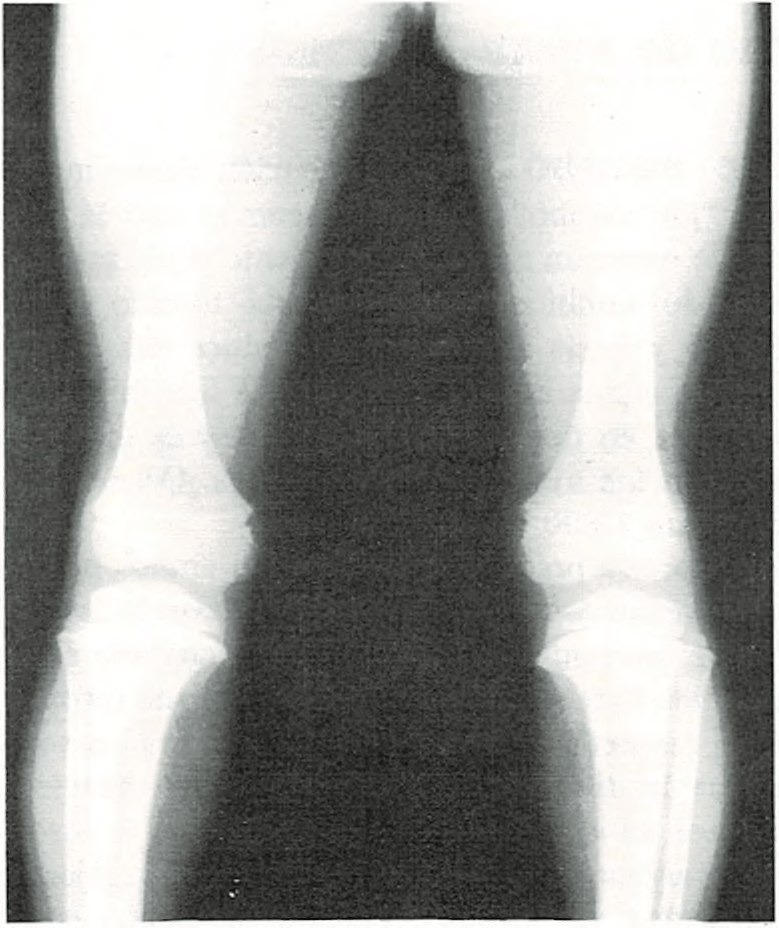

Piernas arqueadas.

Casi todos los recién nacidos parecen tener las piernas curvas. Las rodillas

se hallan dirigidas hacia fuera y los pies ligeramente vueltos hacia dentro. A pesar de que los huesos generalmente están bien formados, las piernas tienden a seguir adoptando la posición que tenían en el claustro materno.

Las piernas curvas no desaparecen en el niño hasta al cabo de un cierto tiempo de caminar. Deben enderezarse primero el tobillo y los músculos del pie, así como los músculos y ligamentos de sus piernas y rodillas. A medida que los músculos se fortalecen al andar, las piernas van apareciendo más rectas y las rodillas más juntas. La edad media en la cual desaparece la incurvación de las piernas es entre 1 y 2 años.

Si tiene las piernas excesivamente incurvadas o si a los dos años no se han enderezado, se consultará al médico.

En algunos casos, las piernas incurvadas pueden estar provocadas por un raquitismo, producido por deficiencia alimenticia de vitamina D. Sólo raramente será necesario un tratamiento especial con ortopedia o cirugía.